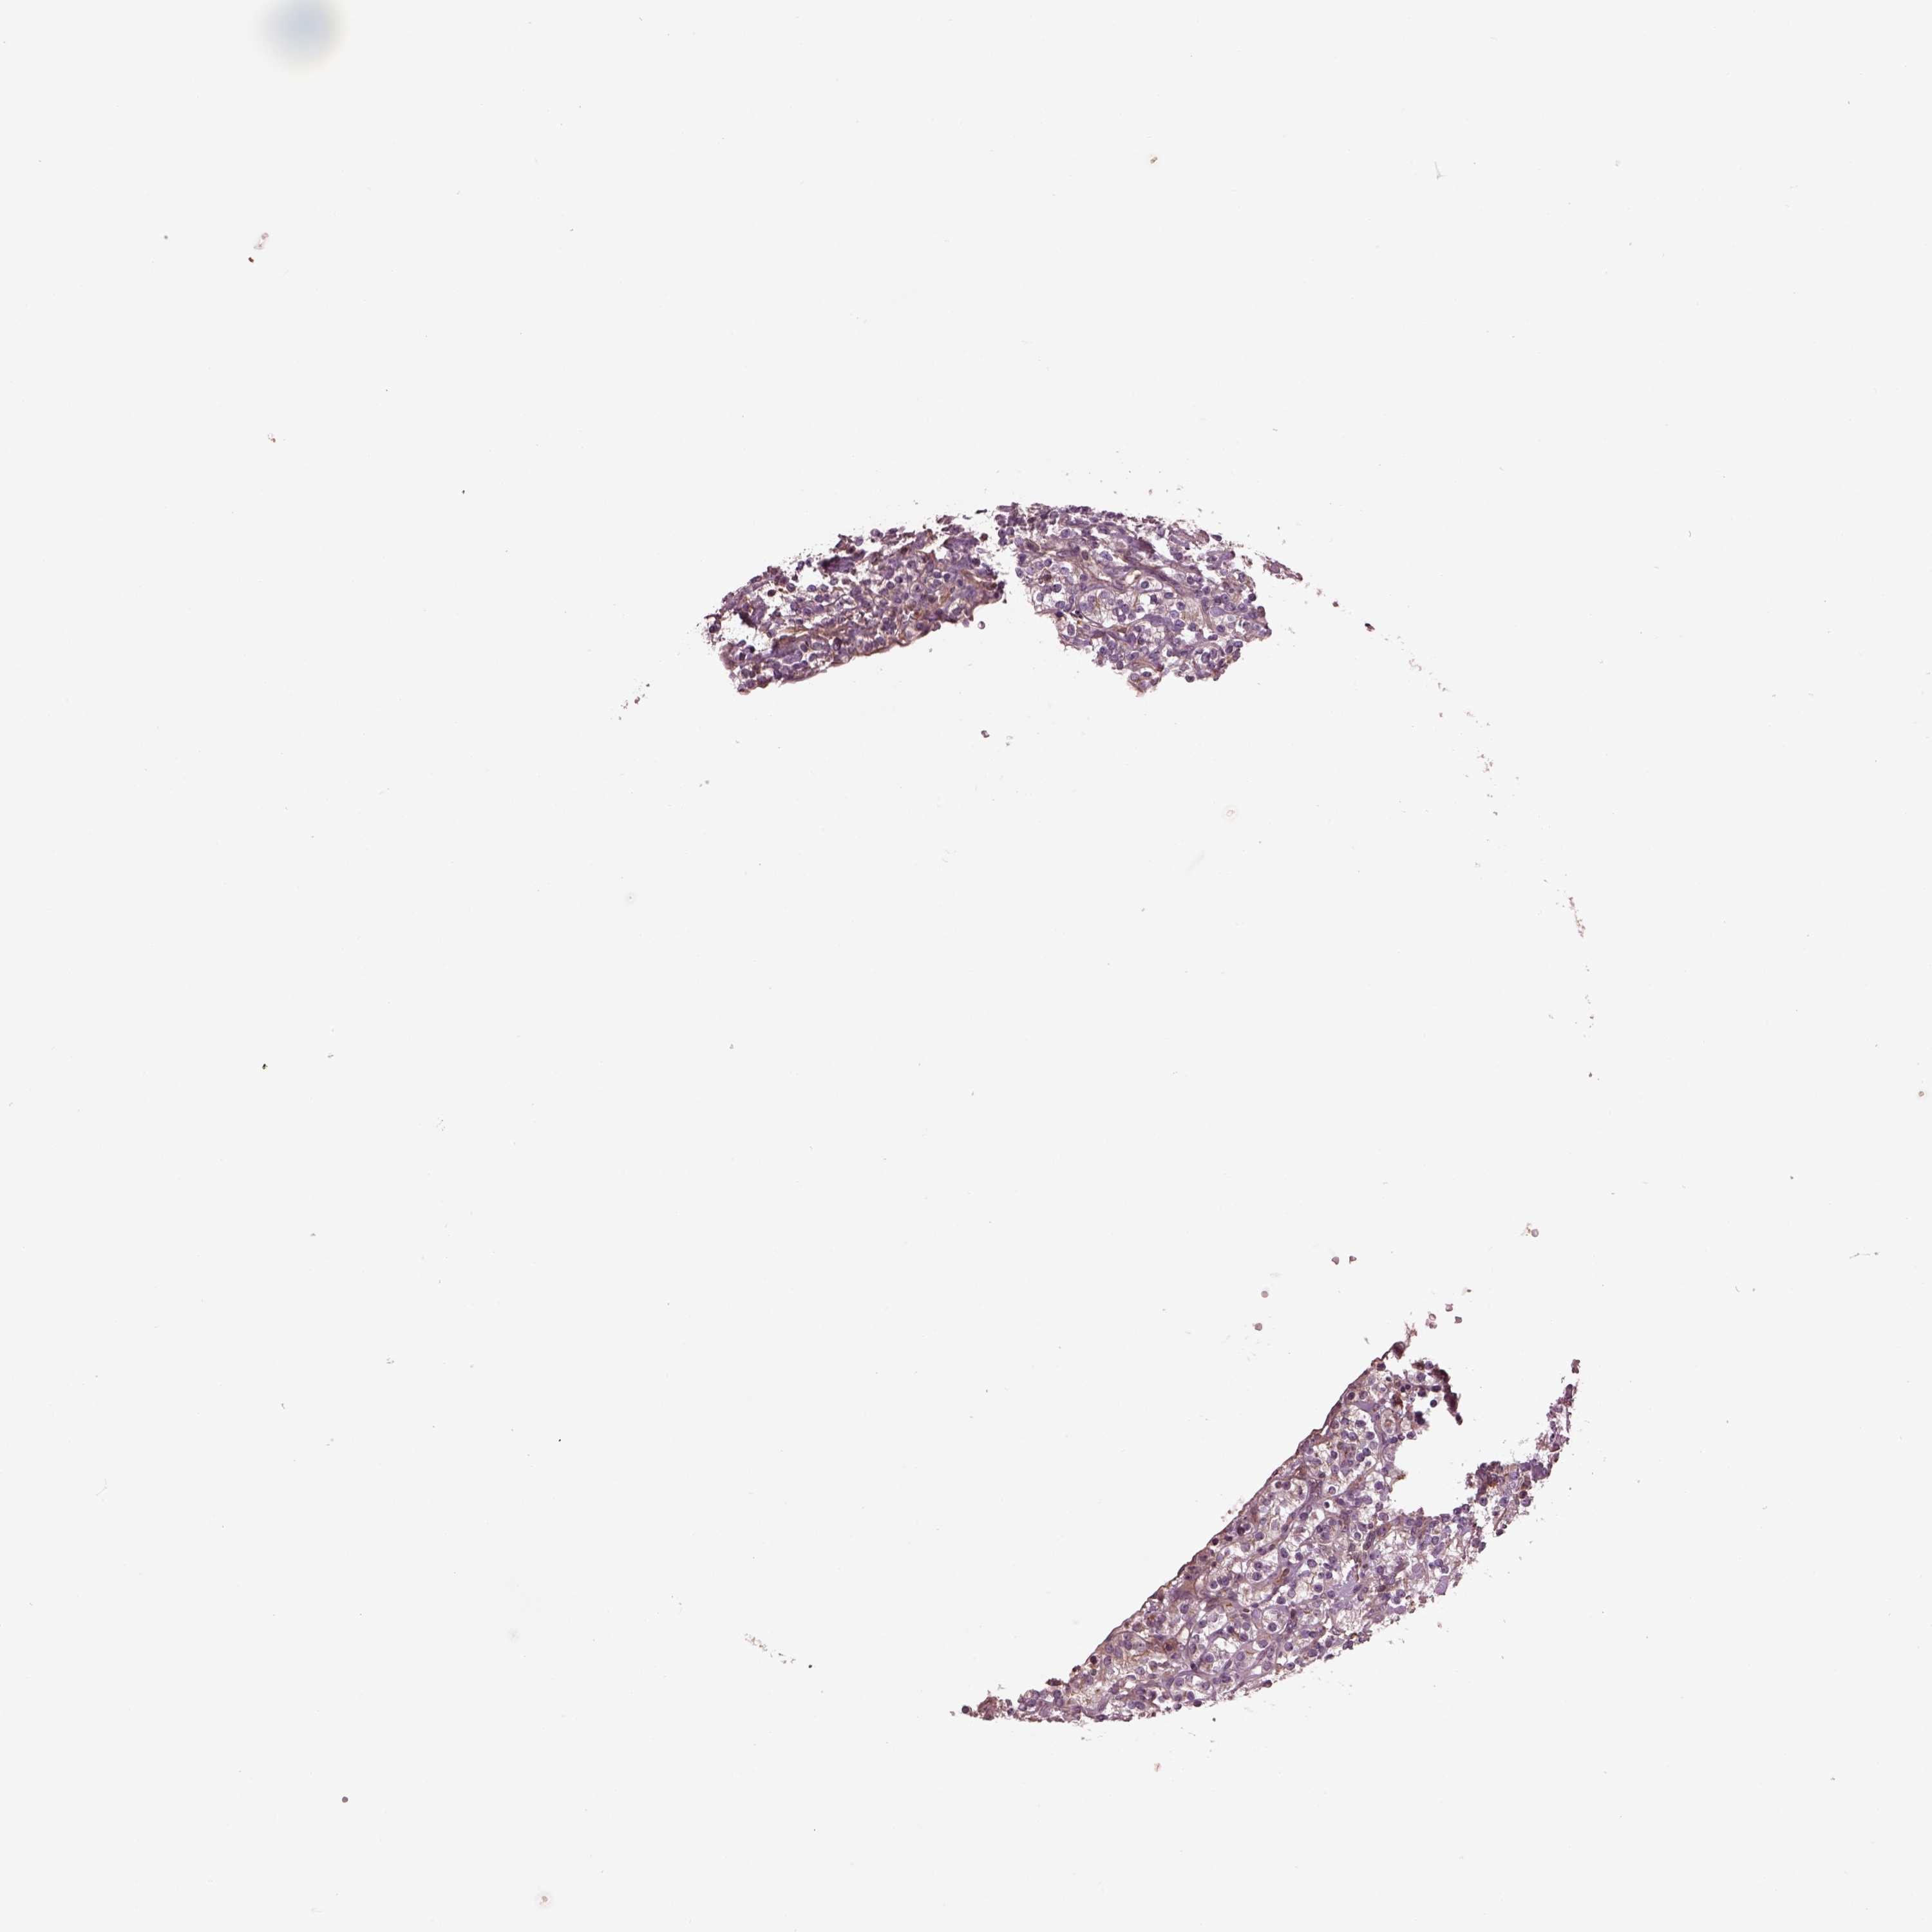

KIDNEY RENAL CLEAR CELL CARCINOMA (VALIDATION) - Interactive survival scatter ploti

The Survival Scatter plot shows the clinical status (i.e. dead or alive) for all individuals in the patient cohort, based on the same data that underlies the corresponding Kaplan-Meier plots. Patients that are alive at last time for follow-up are shown in blue and patients who have died during the study are shown in red.

The x-axis shows the expression levels (FPKM) of the investigated gene in the tumor tissue at the time of diagnosis. The y-axis shows the follow-up time after diagnosis (years). Both axes are complimented with kernel density curves demonstrating the data density over the axes. The top density plot shows the expression levels (FPKM) distribution among dead (red) and alive patients (blue). The right density plot shows the data density of the survived years of dead patients with high and low expression levels respectively, stratified using the cutoff indicated by the vertical dashed line through the Survival Scatter plot. This cutoff is automatically defined based on the FPKM cutoff that minimizes the p-score. The cutoff can be changed by dragging the vertical line or by entering a cutoff value in the square labeled "Current cut-off".

Under the Survival Scatter plot the p-score landscape (black curve; left axis) is shown together with dead median separation (red curve; right axis). Dead median separation is the difference in median mRNA expression between patients who have died with high and low expression, respectively. It is calculated as follows: median FPKM expression of dead patients with high expression - median FPKM expression of dead patients with low expression. This is intended to aid the user in visually exploring custom cutoffs and the associated p-scores and dead median separation.

Individual patient data is displayed and can be filtered by clicking on one or more of the category buttons on the top of the page. Categories describing expression level and patient information include: high, low, alive, dead, female, male and tumor stages. The scale of the x-axis can be toggled between linear and log-scale by clicking on the "x log" button. Mouse-over function shows TCGA ID, patient information and mRNA expression (FPKM) for each patient.

& Survival analysisi

Kaplan-Meier plots summarize results from analysis of correlation between mRNA expression level and patient survival. Patients were divided based on level of expression into one of the two groups "low" (under cut off) or "high" (over cut off). X-axis shows time for survival (years) and y-axis shows the probability of survival, where 1.0 corresponds to 100 percent.

CDC42 is not prognostic in Kidney Renal Clear Cell Carcinoma (validation)

Best expression cut offi

Based on the FPKM value of each gene, patients were classified into two groups and association between prognosis (survival) and gene expression (FPKM) was examined. The best expression cut-off refers the FPKM value that yields maximal difference with regard to survival between the two groups at the lowest log-rank P-value. Best expression cut-off was selected based on survival analysis .

When clicking on this number, the vertical dashed line indicating cut-off, the interactive survival plot, and the Kaplan-Meier curve will be adjusted to show results based on the best expression cut-off.

: 215.72

TCGA RNA samplesi

RNA-seq data is reported as average FPKM (number Fragments Per Kilobase of exon per Million reads), generated by the The Cancer Genome Atlas (TCGA) .

Normal distribution across the dataset is visualized with box plots, shown as median and 25th and 75th percentiles. Points are displayed as outliers if they are above or below 1.5 times the interquartile range. FPKM values of the individual samples are presented next to the box plot.

Average pTPM 193.4

Number of samples 100